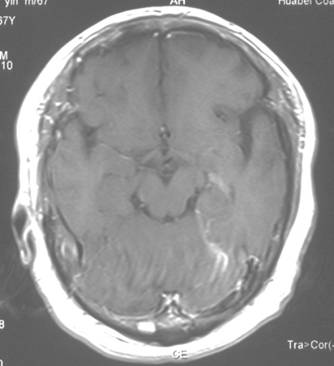

视交叉胶质瘤:

治疗前

治疗后